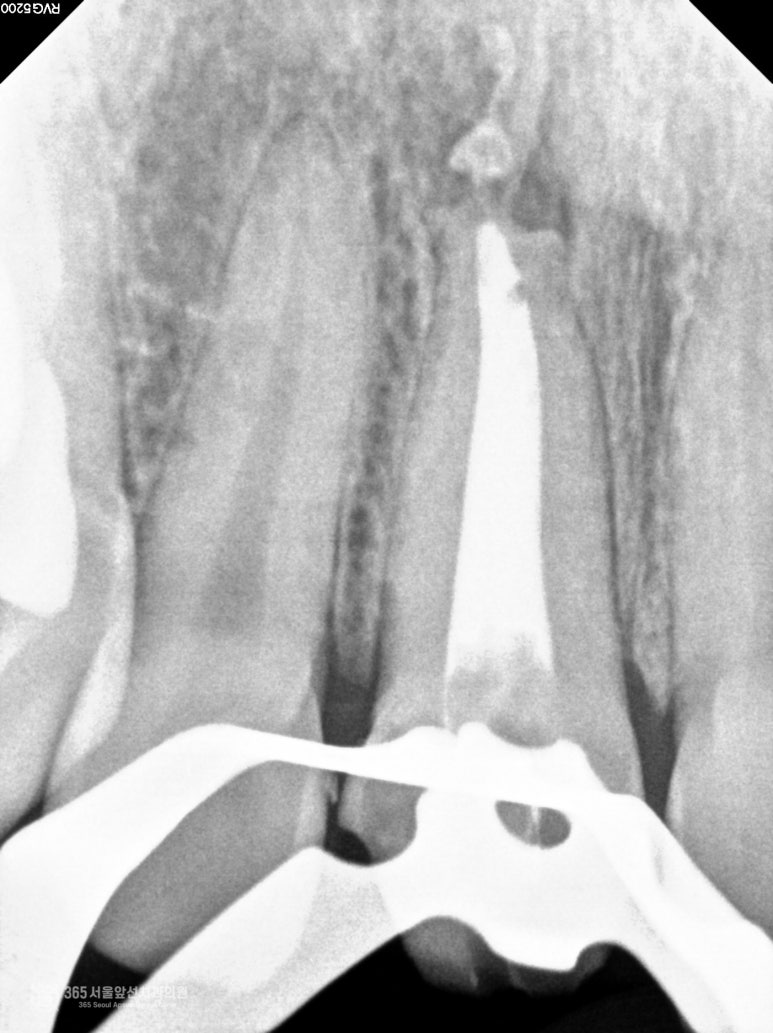

촬영일시 : 2024.10.15 즉 이로 인해 주안동치과추천 365서울앞선치과의원에서 재신경치료를 받게 되었는데요. 재신경치료를 마치고 나서 찍은 엑스레이 사진입니다. 신경치료가 깔끔하게 완료된 모습이 관찰해 보실 수 있습니다.